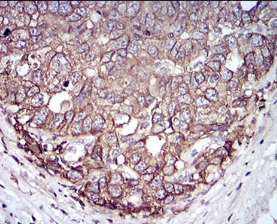

EPCAM Mouse Monoclonal antibody[7B5C1]

IHC    1/200 - 1/1000